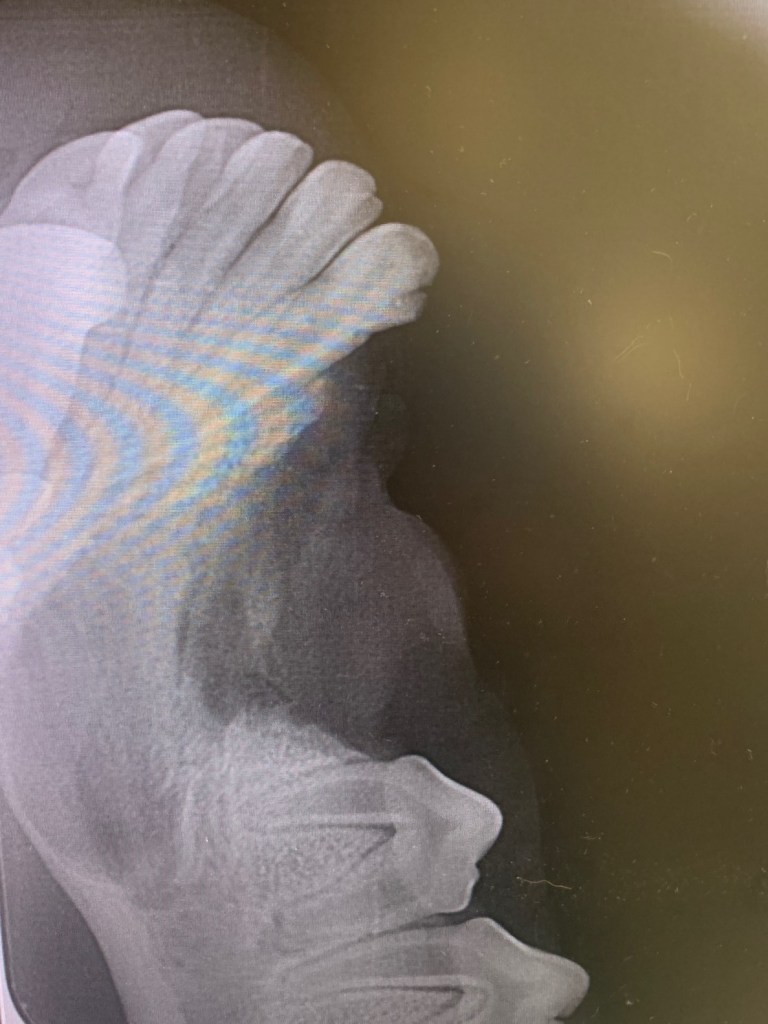

Post op x-ray after extraction

To extract the retained canine tooth alveolar bone was burred away and the two mesial premolars 305 and 306 extracted to allow visualization and access to 304. A vet tome instrument, luxators and elevators were then carefully used to stretch and lance the periodontal ligament around the root. Post extraction the socket was debrided and flushed with saline then a bone graft material (Synergy) was placed in the empty socket. The site was sutured using 4/0 absorbable suture material.

The dog was not allowed to chew on hard substances for 4 weeks to allow time for new mandibular bone to form and the jaw to strengthen. This is because the retained tooth was large and also sitting very close to the mandibular cortex.